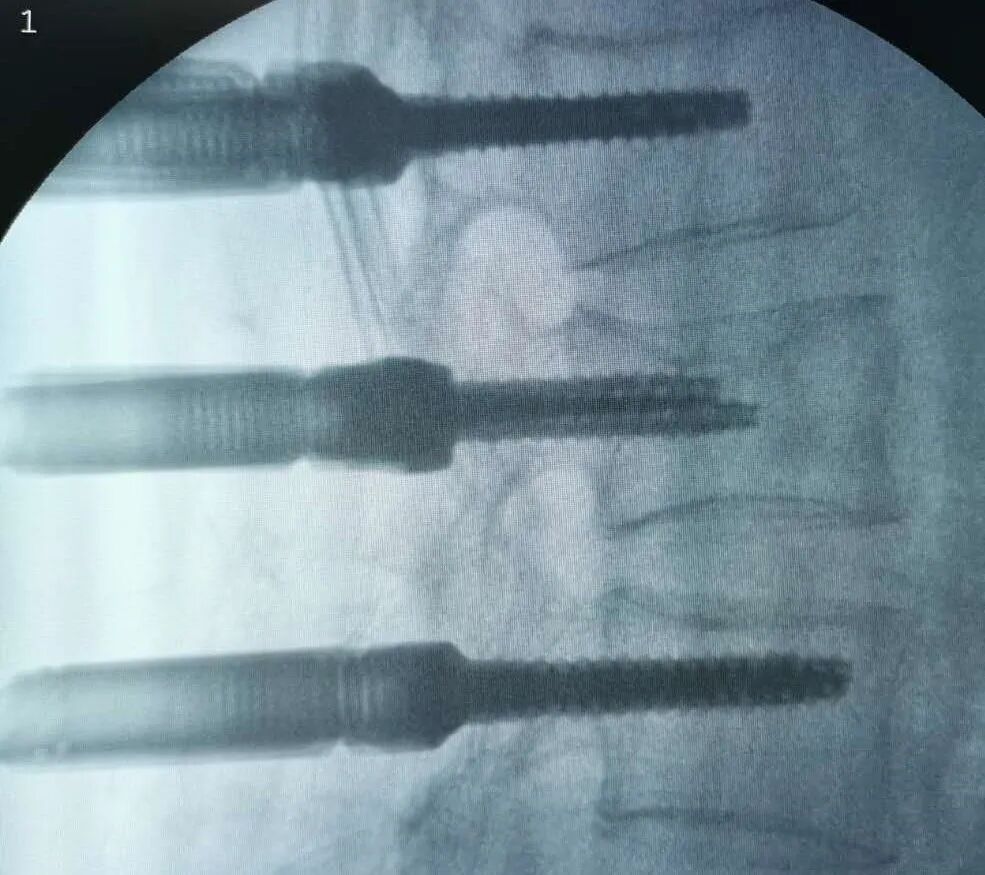

54岁的丁先生,在工地干活时不慎从2米高的高处坠落,臀部着地,当时丁先生只觉得腰部剧痛,不能自如活动,随即由工友送到了海宁康华医院骨2科就诊。 经过CT检查,发现丁先生腰1椎骨折,压缩了约1/2,需要立即采取手术。 丁先生考虑到自己是家中重要的劳动力,强烈要求采取创伤小、恢复快的方案进行治疗,以便自己尽快恢复工作。骨2科团队经过认真研究,决定采用微创小切口的方式在脊柱后路用钉棒固定丁先生因骨折压缩的腰1椎体。最终手术顺利完成。 术后经过复查,CT图像提示腰椎高度回复,内固定位置良好,一周后即可下床。 康华医院骨2科主任、副主任医师陈杰介绍,传统处理腰椎骨折手术需要切开皮肤,剥离肌肉,显露椎体结构后,植入椎弓根螺钉固定,存在切口长、椎旁肌肉剥离广泛、术中出血多、术后切口引流量大、术后切口疼痛、恢复期长等一系列的问题。 而像丁先生这样采取经皮微创植入椎弓根钉棒固定的手术,因其手术创口小(约1cm*6),术中出血少,不剥离椎旁肌肉,术后切口无需引流,无术后切口疼痛,可早期下地进行功能恢复,是近年来发展起来一项技术,也是近年来治疗腰椎滑脱、胸腰椎骨折、椎管狭窄等脊柱疾病采用的一种手术方式。 因为是微创技术,对手术技术要求比传统手术方式更高,术前需要非常周密的计划,根据患者的影像资料做非常精确地测量和定位,更需要手术医生具有非常娴熟技术,因此之前只有一些三甲大医院才有开展。近年来,骨2科在陈杰主任带领下,刻苦钻研,不懈追求,不断精进,希望能以更精湛的技术,温馨的服务,竭力为广大患者解除病痛。